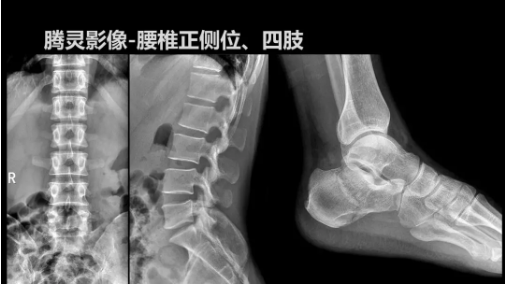

2019年10月19日,82屆秋季CMEF于青島世博城國際展覽中心如期舉辦,國內(nèi)動態(tài)DR領(lǐng)域的佼佼者安健科技攜新品——“騰靈”多功能診斷專用動態(tài)DR亮相展會現(xiàn)場。

“騰靈”是安健科技的第四代動態(tài)DR產(chǎn)品,可實現(xiàn)全科室應(yīng)用。如各類常規(guī)的X線檢查、消化道檢查、骨科檢查、婦科、兒科檢查等。此外,安健科技為“騰靈”在真正意義上實現(xiàn)多科室、多功能診斷進行了多項針對性設(shè)計。

其中包括SID范圍可調(diào)節(jié)能夠滿足多種類攝影要求、球管角度可調(diào)節(jié)能夠滿足不同投照部位的需求、超低床體設(shè)計方便患者上、下床、360°可旋轉(zhuǎn)腳踏板降低擺位難度、可移除式濾線柵能夠滿足兒科等特定場景的計量要求、可升降操控臺方便醫(yī)生床旁操作等,并配置了全身拼接功能,最大程度上適配動態(tài)DR產(chǎn)品的特點。

相較前代產(chǎn)品,“騰靈”在圖像質(zhì)量方面得到了全面升級,“騰靈”采用17*17非晶硅平板探測器設(shè)計,采集矩陣達(dá)3072*3072,動態(tài)范圍達(dá)16bit,為成像提供超大視野的同時保證成像質(zhì)量,此外,該款機型可根據(jù)醫(yī)療機構(gòu)的差異化需求而選配不同的動態(tài)平板探測器,以此來適應(yīng)不同階層用戶所需。